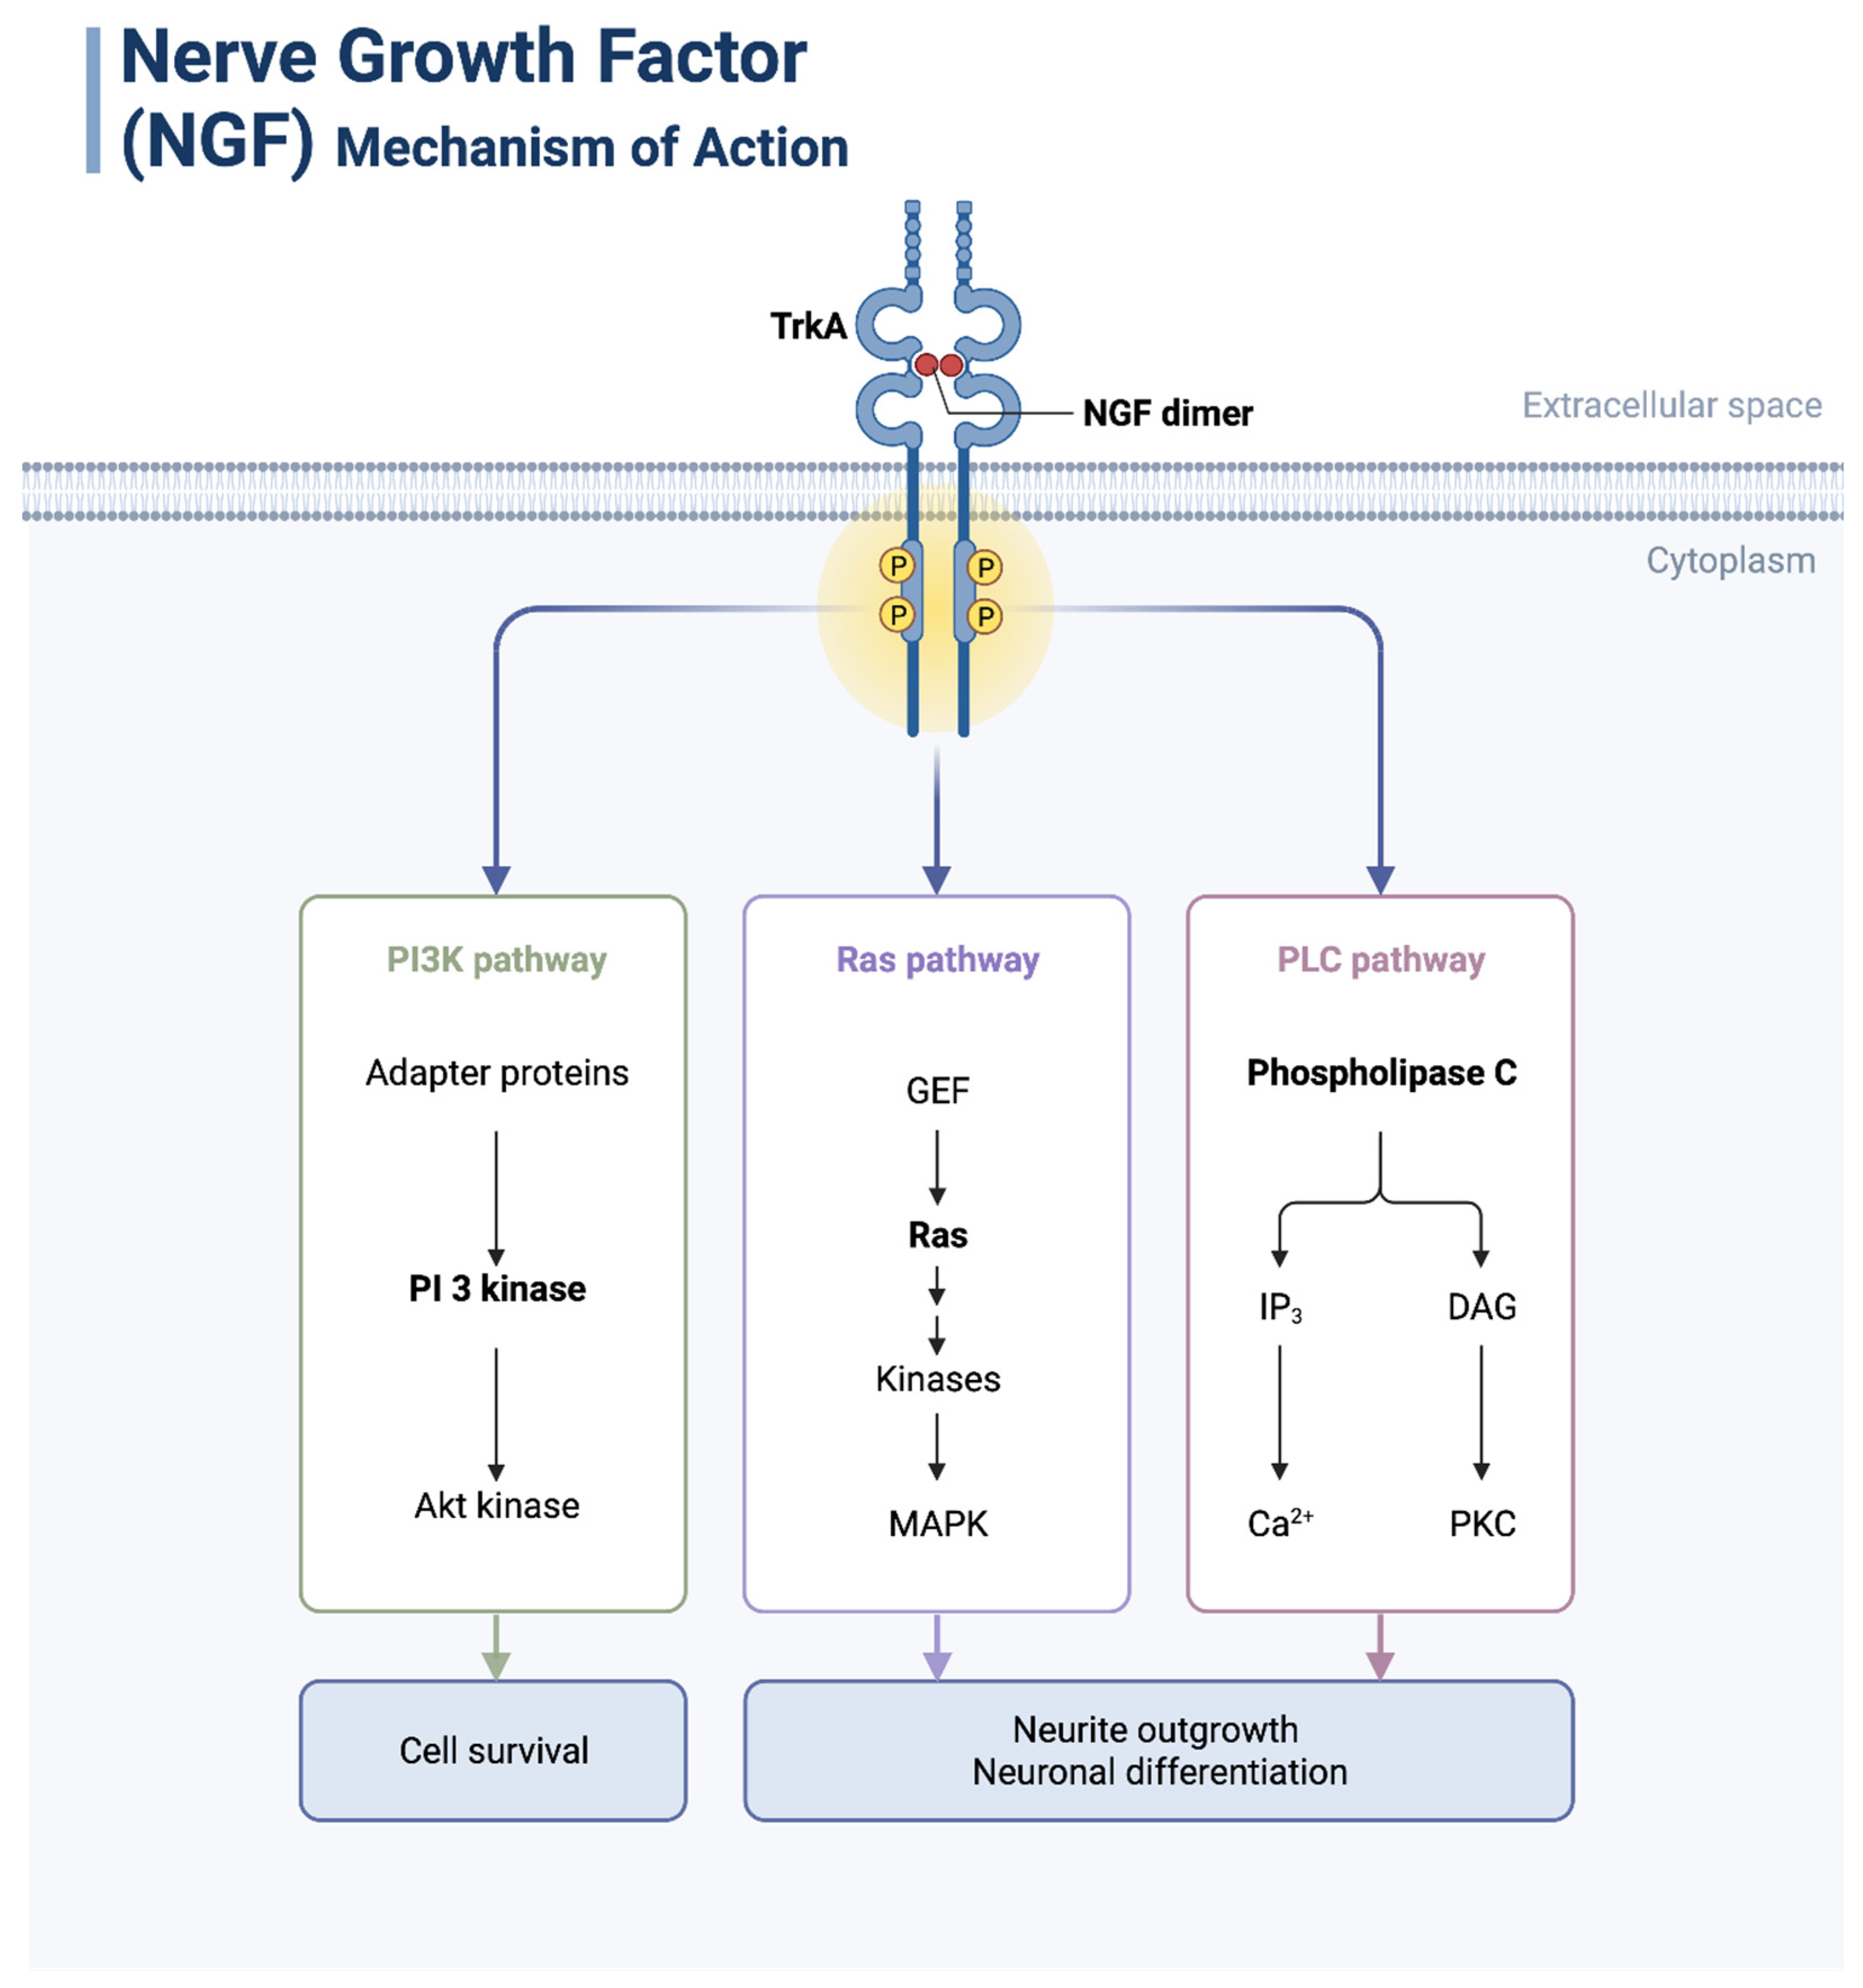

3. Neurotrophic Factors and Their Functions and Expression Patterns in Cancer

3.1. NGF